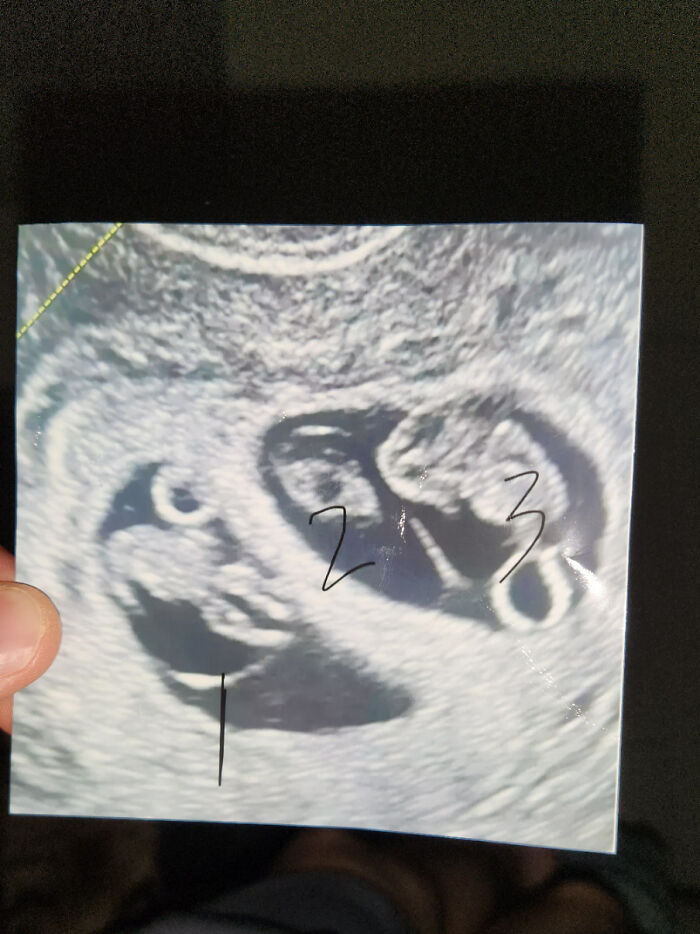

Buckling In, Fellow Dads. Have A 2.5 Year Old Girl And Wife Is Pregnant With Triplets. Completely Spontaneous